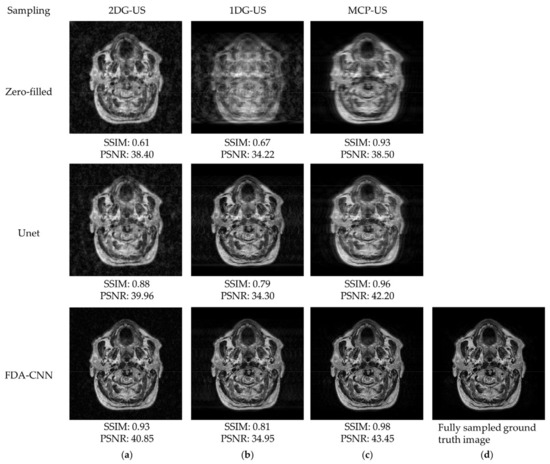

4.1. BraTs 2020-T1 Dataset